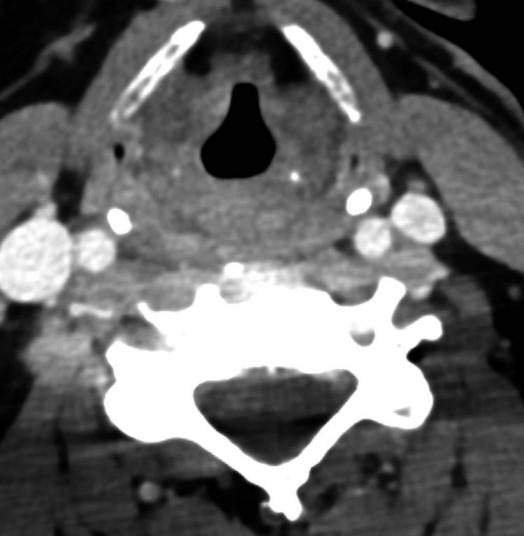

等级、粗糙度、呼吸、乏力、劳损(GRBAS)量表为G3 R3 B2 A1 S2。平均基频高于正常范围。低至高频谱比的测量值低于正常范围,发音困难的倒谱频谱指数(CSID)显著增加。当与声信号中的其他噪声测量值(抖动百分比、闪烁百分比和噪声谐波比)相结合时,支持该诊断。音调范围高于正常范围,响度范围减小。空气动力学评估显示,呼气量减少,最大发声时间显著缩短,平均峰值气压显著增加,发声阈值压力显著增加,表明发声努力增加。颈部CT增强扫描显示水肿涉及真声带和假声带、会厌皱襞、声门旁脂肪,以及相关的梨状窝粘膜增强(图2)。

图2:颈部CT对比显示水肿,累及真声带、假声带、会厌褶襞和声门旁脂肪